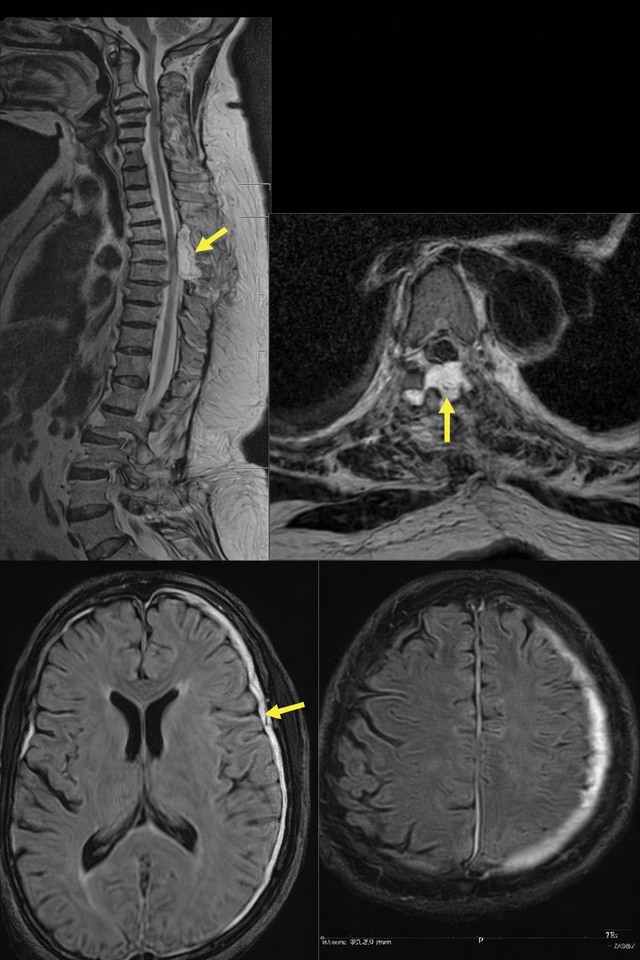

Remote intracranial hemorrhage after supratentorial and spinal surgery: a three case series and review of literature